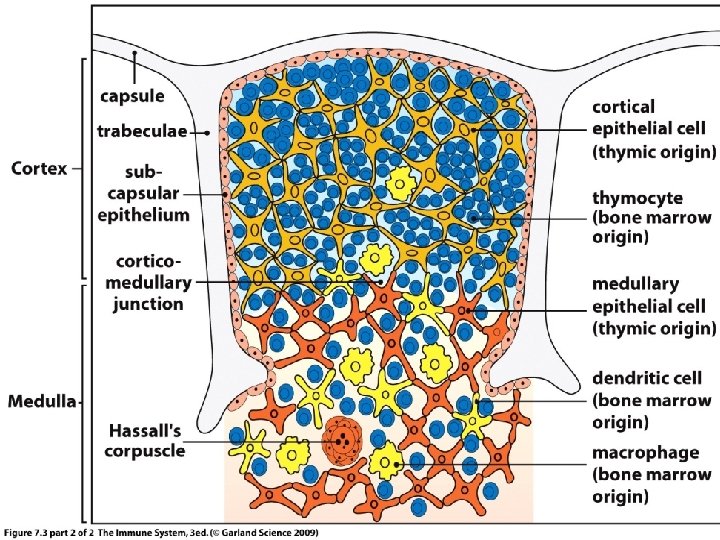

Thymus is the only discrete central lymphoid organ in humans. It produces only T lymphocyte precursors and has no lymphoid nodules. Its reticular cells derive from endoderm and produce no reticular fibers. It is the only organ containing Hassall’s corpuscles. Its age-dependent structural atrophy or involution is also unique among lymphoid organs. 2 lobes are joined and covered by a thin loose connective tissue capsule that penetrates the lobes as septa, dividing each lobe into incomplete lobules. Cortex. This is the dark-staining periphery of each lobule. Small lymphocytes predominate

Medulla. In effect, each thymic lobe has a single medulla that extends into the core of each of the lobules. The light staining of the medulla reflects the presence of more epithelial reticular cells and fewer lymphocytes than in the cortex. The spheric Hassall’s corpuscles (30 -150 m in diameter) are composed of concentric layers of flattened epithelial reticular cells. With age, cells in the core of the corpuscles may die and calcify. Functions: 1. T lymphocyte production. 2. Blood -thymus barrier. 3. Production hormone - thymosin